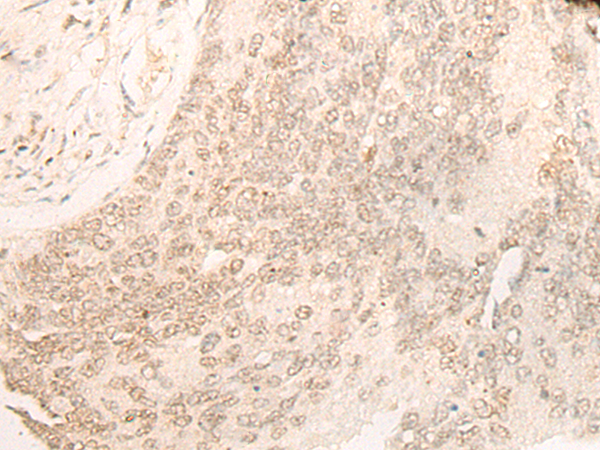

分类: 科研抗体货号: P13219别名: CDP; CUX; p75; CASP; CDP1; COY1; Clox; p100; p110; p200; CUTL1; GOLIM6; CDP/Cut; Cux/CDP; Nbla10317应用: IHC反应种属: Human, Mouse, Rat